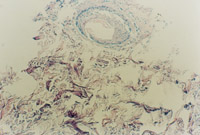

3-23 對其“皮點(diǎn)”進(jìn)行組織學(xué)檢查,該組織為從皮下組織中再生出的微血管、膠原組織、表皮細(xì)胞組織組成的再生皮膚組織團(tuán)